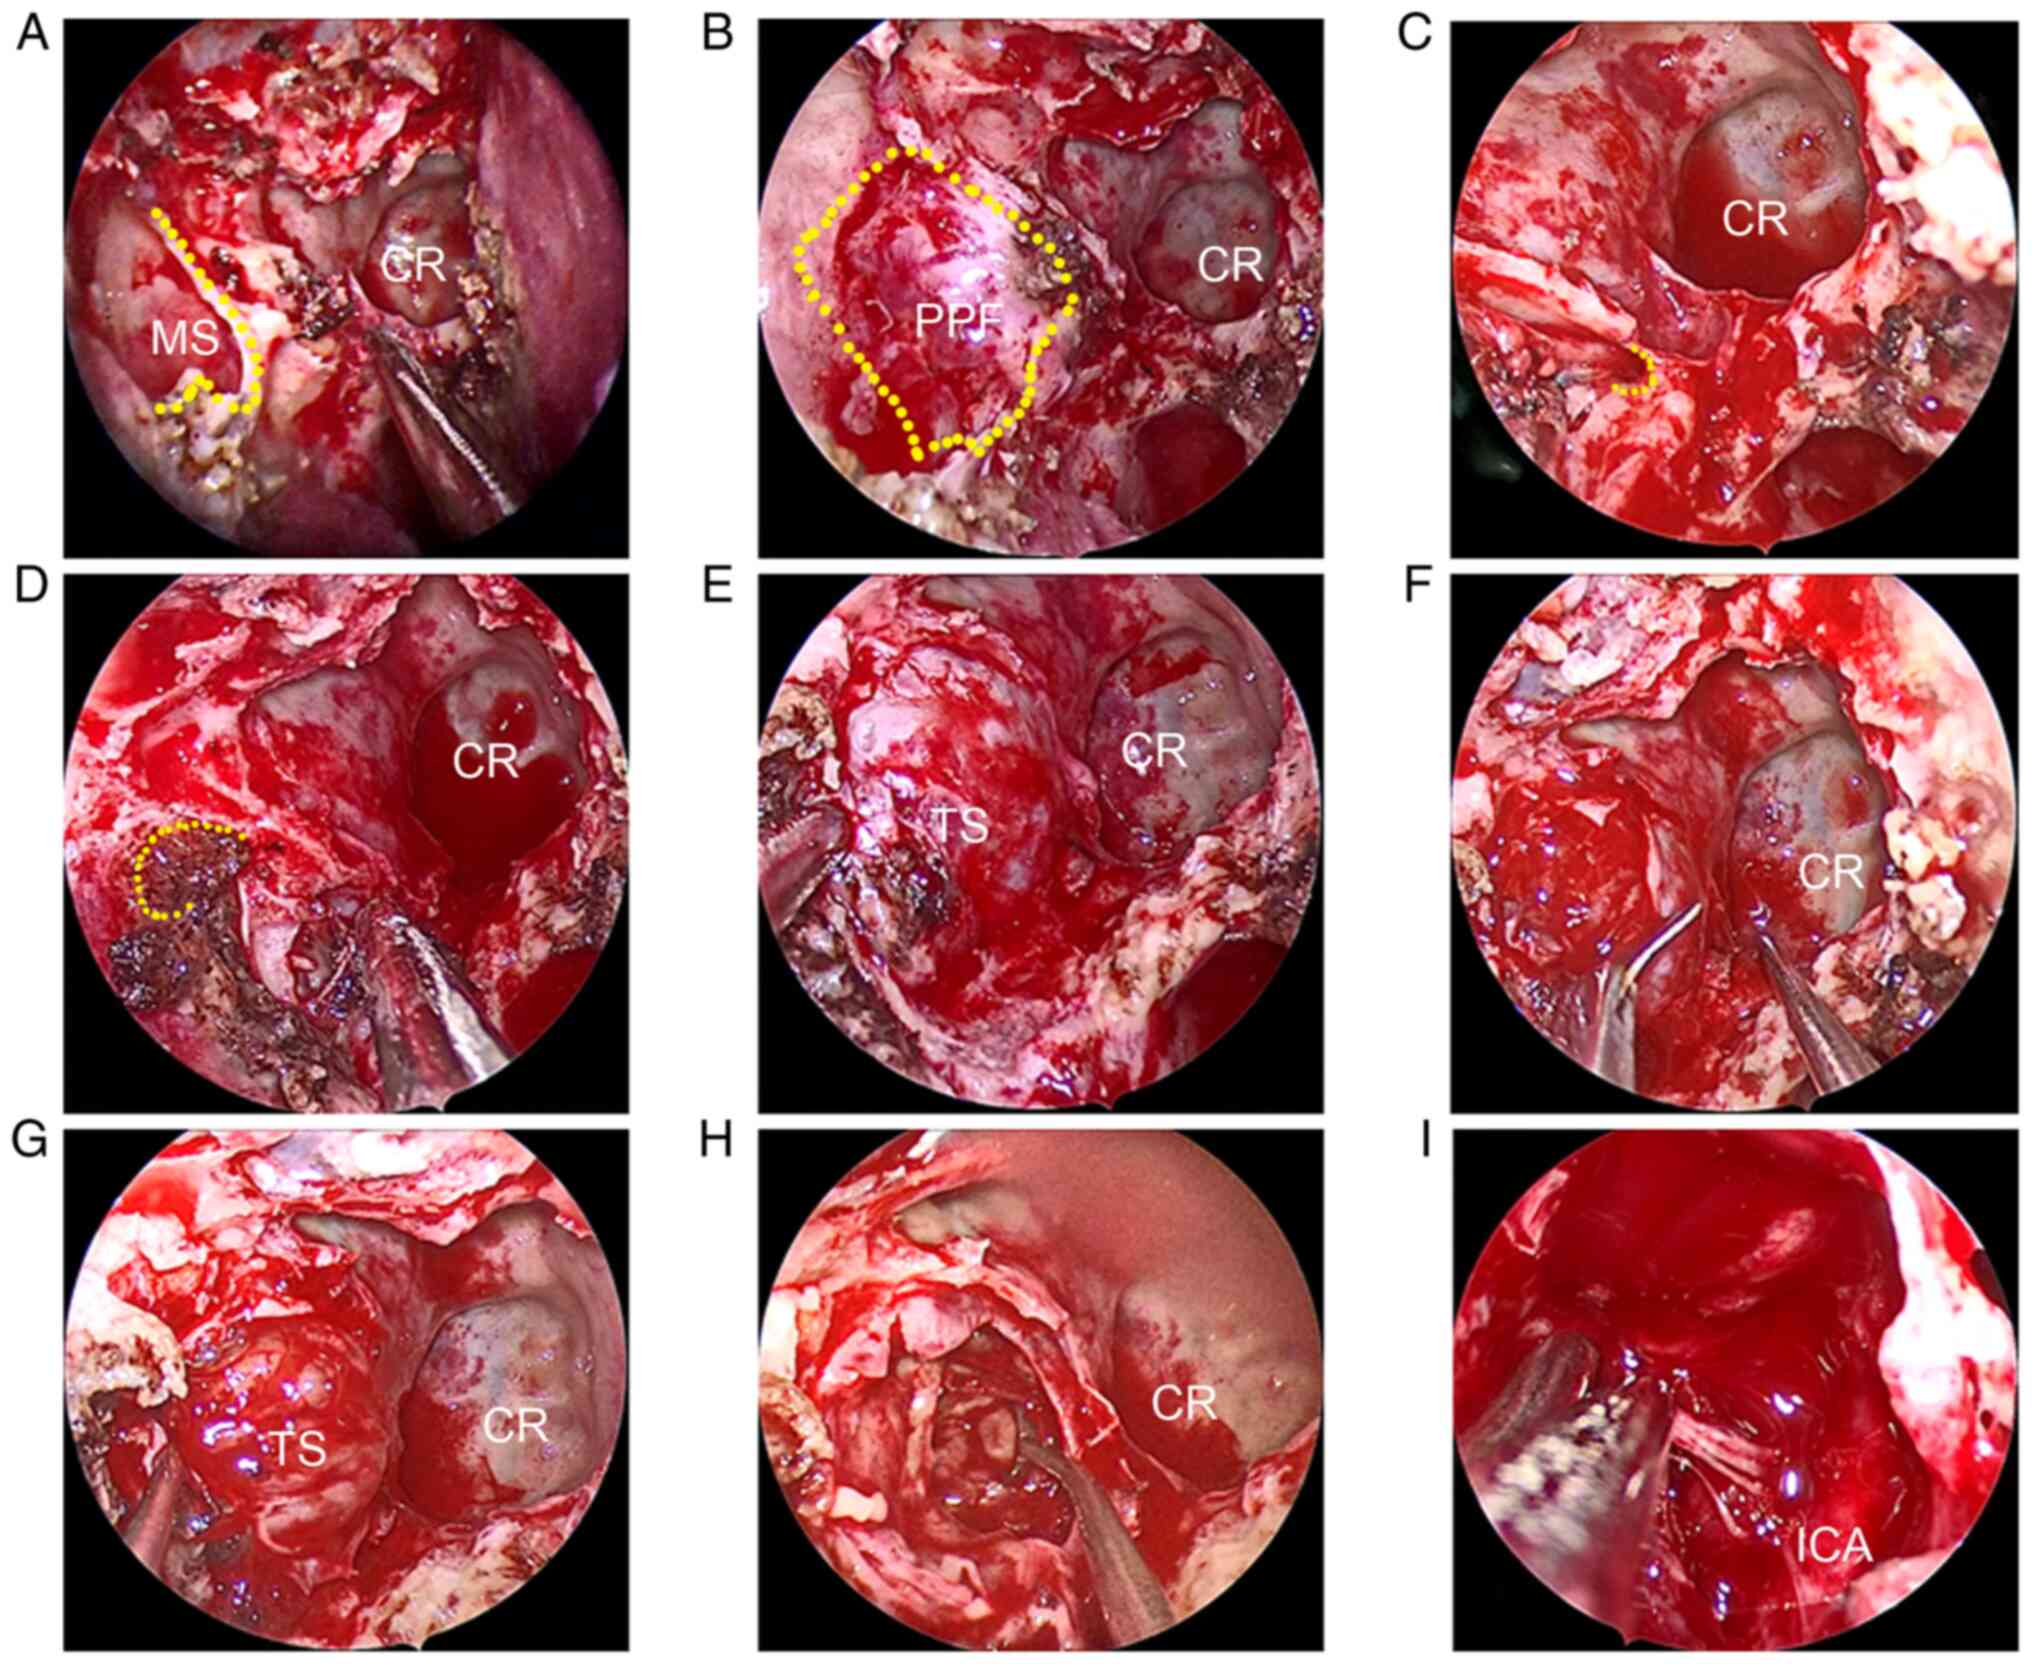

Figure 2

Endoscopic resection of the TS in the right middle cranial fossa through the transnasal maxillary sinus approach. (A) Endoscopic 0˚ lens entered the right meatus nasi medius and enlarged the opening of the MS (yellow dotted line indicates the edge of MS). (B) Removal of the posterior wall of MS and exposure of the PPF (yellow dotted line indicates the PPF zone). (C) Disposal of the nerves and vessels in PPF and further exposure of the opening of the Vidian canal. The yellow dotted line indicates the opening of the Vidian canal. (D) Position of the foramen rotundum was determined (yellow dotted line indicates the opening of the foramen rotundum. (E) Enlarged foramen rotundum and removal of bone from the skull base; the TS was located in the middle cranial fossa. (F) The dura was incised and the body of the tumor was exposed. (G) TS was peeled from surrounding tissues. (H) Intratumoral decompression and piecemeal resection of the tumor. (I) After the TS was totally resected, a vertical segment of the ICA was displayed. CR, clival recess; ICA, internal carotid artery; MS, maxillary sinus; PPF, pterygopalatine fossa; TS, trigeminal schwannoma.